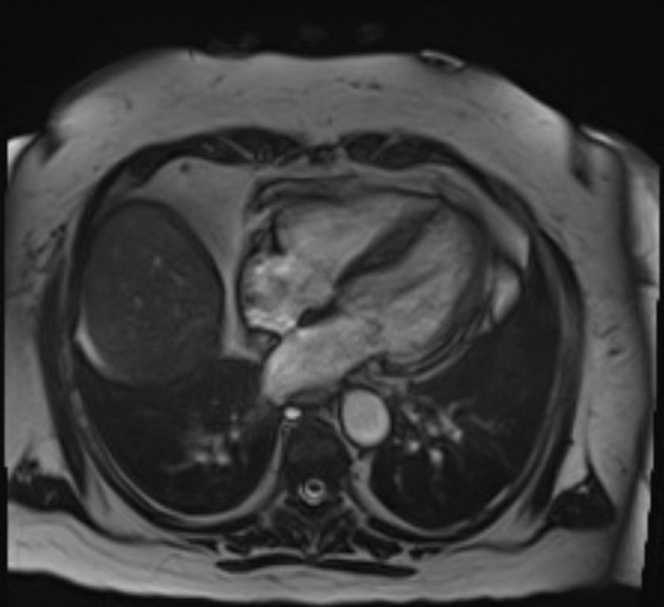

Cardiac magnetic resonance performed on day 13 of presentation showed normal left ventricular size with preserved overall ejection fraction and apical hypokinesis (Figure 3). There were large areas of increased T1 and T2 signal consistent with acute myocardial edema, without significant late gadolinium enhancement. A small area of basal lateral contrast uptake suggested minimal fibrosis or a prior infarct.

Figure 3.

Cardiac Magnetic Resonance With Gadobutrol Contrast Showing Normal Left Ventricular Size With Preserved Left Ventricular Ejection Fraction and Hypokinesis of the Apical Segment of the Left Ventricle

Given the markedly elevated cardiac troponin levels, ST-segment elevation on ECG, and cardiogenic shock, she was initially diagnosed with ST-segment elevation myocardial infarction; however, the left heart catheterization ruled against it. The leukocytosis on presentation and past medical history of extensive autoimmune diseases raised the suspicion of myocarditis. The cardiac magnetic resonance performed on day 13 did not show any findings consistent with myocarditis.

The patient's hemodynamic status improved gradually with intensive supportive care. Serial imaging demonstrated recovery of ventricular function, and the final diagnosis of TTC was confirmed based on cardiac magnetic resonance. On a follow-up echocardiogram performed 4 weeks later, she had complete recovery of LVEF; however, her baseline global longitudinal strain was mildly impaired at −11%.

This report describes rare case of TTC in a postmenopausal woman with a chronic cannabis use who developed cardiogenic shock with CHS. TTC is characterized by transient left ventricular dysfunction in the absence of obstructive coronary disease, typically triggered by physical or emotional stress. Emerging evidence implicates cannabis use as a potential precipitant. Our patient with a history of CHS presented with gastrointestinal symptoms after cannabis use, was found to have severe hypokalemia secondary to intractable vomiting, elevated troponin and NT-proBNP levels, ST-segment elevations on ECG, markedly reduced ejection fraction with left ventricular wall motion abnormalities, and a negative coronary angiography result. Cardiac magnetic resonance performed 2 weeks later demonstrated normalization of the ejection fraction, persistent apical hypokinesis with acute edema, and no contrast uptake consistent with TTC. Notably, she had no identifiable physical or emotional stressor preceding the presentation.